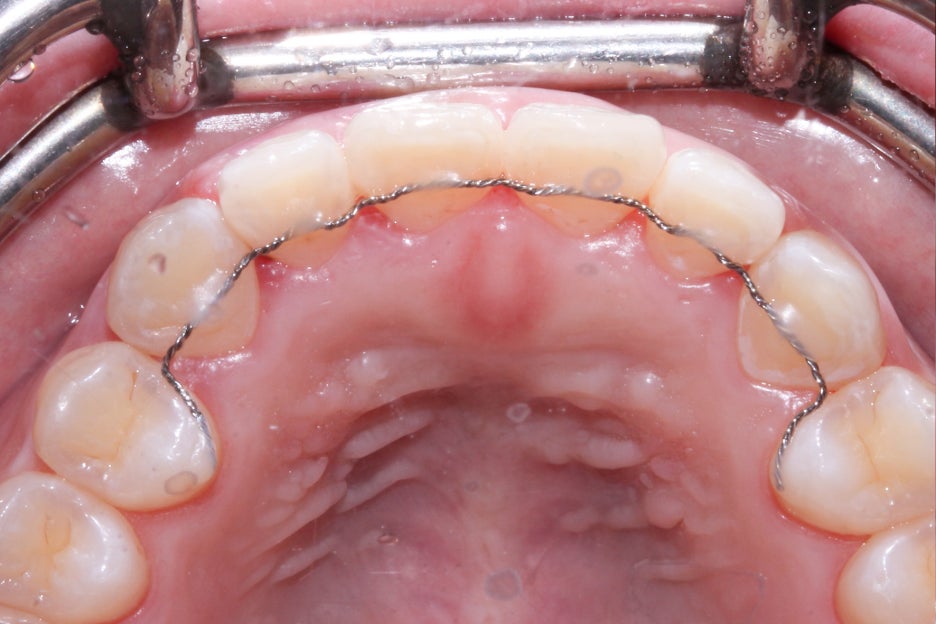

구내사진을 보시면 브라켓을 부착했던 치아들이

모두 고르게 배열된 모습인데요, 부분교정의 경우

일반적인 전체교정보다 치아의 변위가 크지 않고

공간을 닫거나 여는 폭도 좁기 때문에

교정 전과 후의 차이가 명확하지 않을 수 있습니다.

옥니교정 후 중절치의 치축이 바르게 교정된 모습으로

세라믹 부분교정을 진행했던 상악 전치부 6개의 치아들이

모두 가지런해진 것을 확인할 수 있는데요,

교정이 종료된 후에도 유지장치를 반드시 착용하여

치아가 원래의 상태로 돌아가려는 힘을 막는 것이 중요합니다.